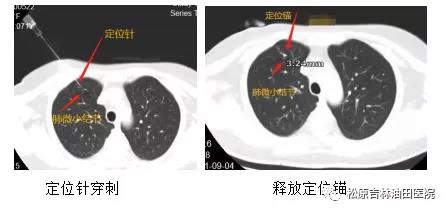

CT定位下肺结节穿刺是利用CT的立体成像技术,在体表对应位置穿入穿刺针,再次CT确认无误后释放锚定装置,从而将肺内微小病灶锁定。 术中采用专用的肺结节定位针,它由一根穿刺针和针管内的一根定位线、定位锚组成,定位锚为四个倒刺结构,倒刺前端圆钝,在保证牢牢钩住肺组织的同时又减少肺组织损伤,医生在胸腔镜下能明确看到病灶部位,从而将结节摘除。 通过CT定位穿刺肺结节,不仅能够切除良性病变,对于早期肺癌,通过局部切除也能够达到治愈的目的。

CT科臧文远医生:“这项技术一般要求将定位锚释放到肺结节旁1cm范围内,由于我科在肺结节穿刺活检基础上开展的这项技术,我们对定位锚释放位置有更高要求,一般我们会把定位锚和病灶距离控制到0.5cm以内,这样术中可以保留更多肺组织。对于肺内微小结节(直径小于0.5cm)我们也能准确定位,临床医生对主病灶进行切除的同时,对其它的一些小病灶一起切除,为患者除掉安全隐患” 。